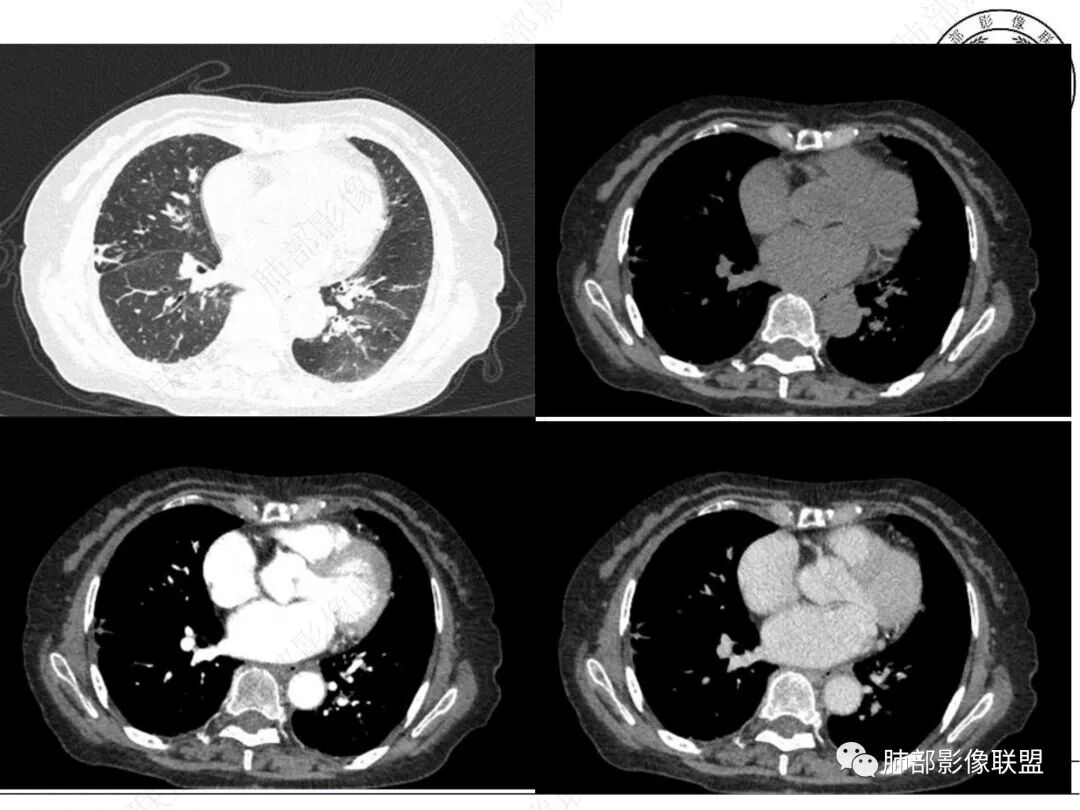

2. CT示右肺上叶多发斑片状实变影,结节影,集群散落,夹杂条索影,边界可分辨,有沿支气管血管束分布趋势,可见树芽征。病灶新旧不等、密度不均。右上叶支气管壁不均匀节段性增厚狹窄,斑点状钙化。纵隔旁部分肺组织含气不良,并显示轻度扩张支气管。病灶邻近胸膜增厚,轻度强化。

3.余双肺显示马赛克灌注、轻度气肿。双肺散在微小实行密度结节影,边界清楚。

4.纵隔多发增大淋巴结,部分融合、钙化。

成簇分布斑片影、结节影、树芽征,边界较清楚,新旧不等,节段性支气管壁增厚伴钙化,管腔狭窄,纵隔及肺门淋巴结增大钙化等都较符合“继发性肺结核、支气管内膜结核”诊断。